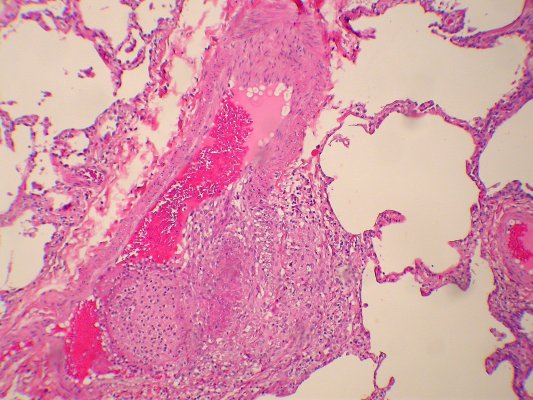

Карнификация Легкого: Микропрепараты и Диагностика

Раздел: Калейдоскоп образов